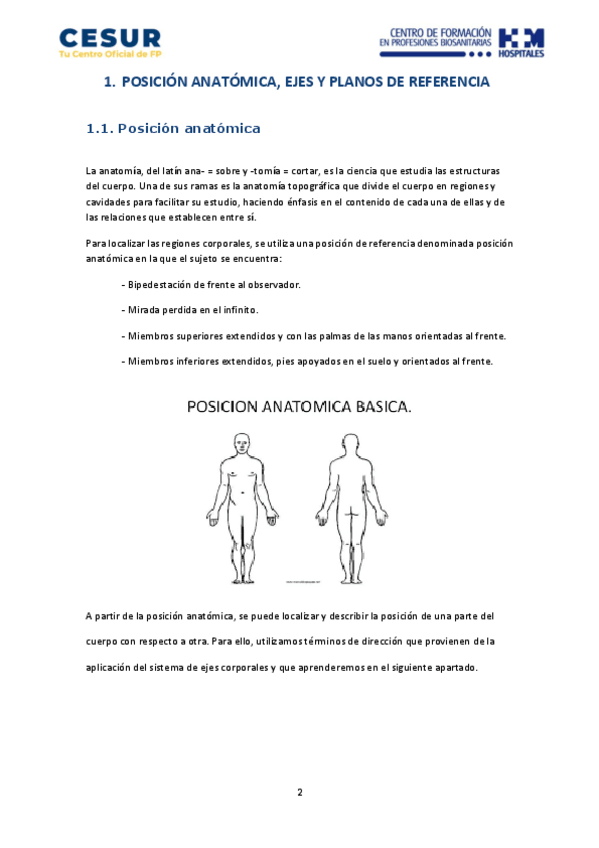

He publicado nuevos apuntes de Anatomía por la Imagen: Tema-1.-Localizacion-de-estructuras-anatomicas.pdf